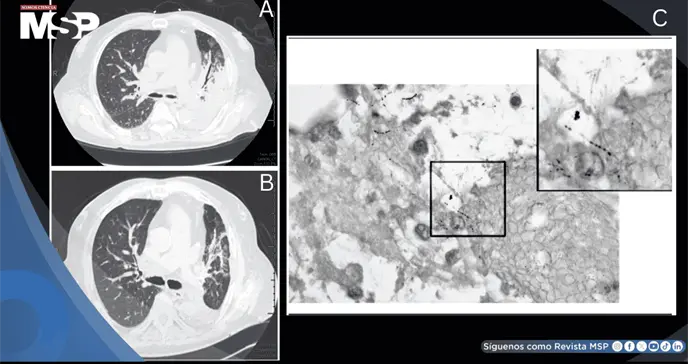

El paciente fue admitido en la unidad de cuidados intensivos médicos con diagnóstico inicial de neumonía severa. Los estudios de imagen revelaron consolidación en el lóbulo inferior izquierdo, compatible con proceso infeccioso. Se inició tratamiento empírico con piperacilina/tazobactam y metilprednisolona sistémica.

A pesar del tratamiento antibiótico de amplio espectro, la condición clínica del paciente continuó deteriorándose. Ante la falta de respuesta terapéutica, se decidió realizar una broncoscopia diagnóstica para obtención de muestras respiratorias directas. Los cultivos de esputo identificaron especies de Nocardia, confirmando el diagnóstico de nocardiosis pulmonar.

Los estudios de imagen de seguimiento demostraron resolución parcial de la consolidación pulmonar. El paciente fue dado de alta con plan de seguimiento ambulatorio estrecho y continuación de la terapia antibiótica prolongada, como se requiere típicamente en casos de nocardiosis.